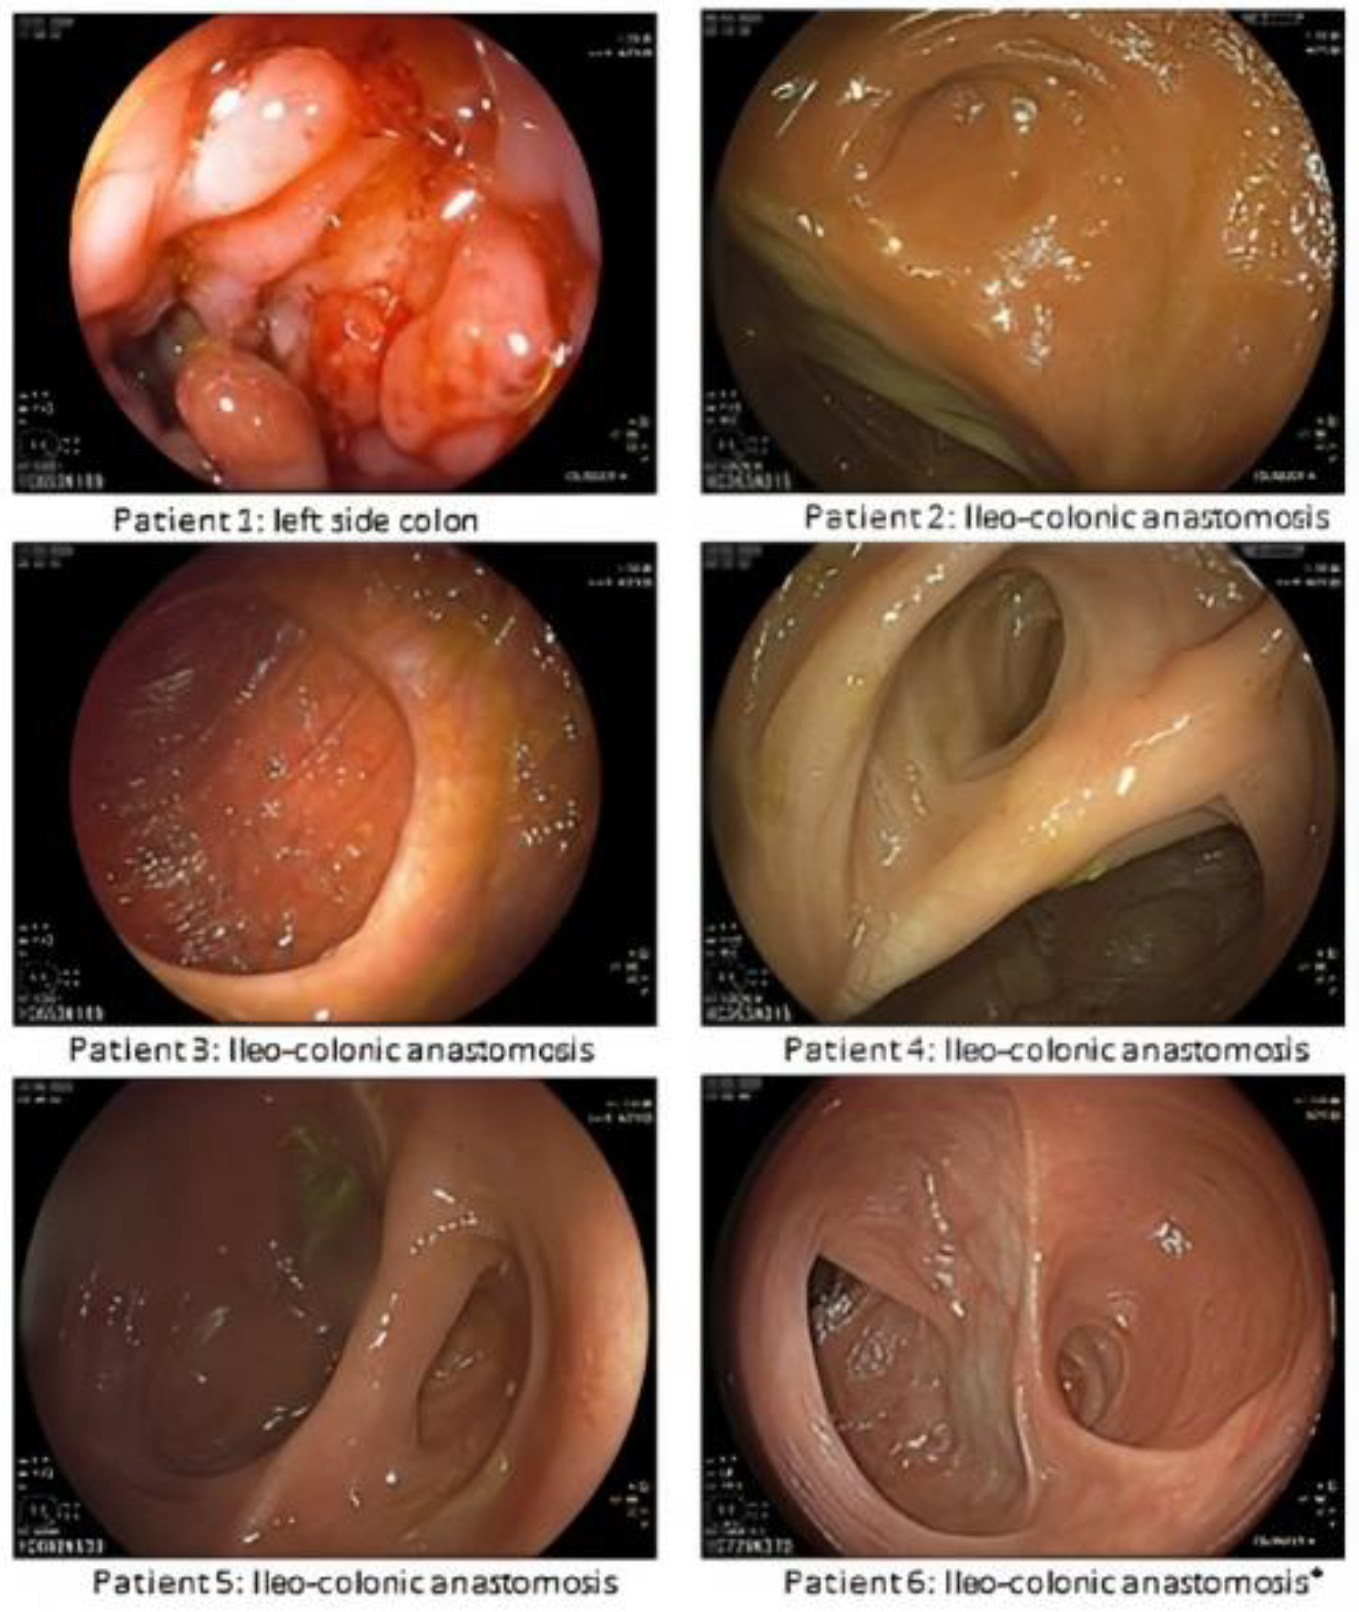

3.2. Endoscopic and Histological Evaluation

| Female | 41 | 9 | Inflammatory stenosis; Active penetrating disease | A3/L3/B3p | ADA | No | 50 | 4 | 0 (10) | i4 (32) | T+: i, lc; E+: i, lc (19) | 33 | Yes (10) |

| Male | 26 | 1 | Inflammatory stenosis | A2/L3/B3 | IFX | No | 27 | 6 | i1 (12) | i0(26) | T−; E+: i (13) | 58 | No (1) |

| Female | 31 | 6 (1st resection) 16 (2nd resection) | Inflammatory stenosis; Active penetrating disease | A2/L3/B3p | IFX; AZA | Yes | 57 | 10 | 0 (8) | 0 (32) | T−; E− (17) | 62 | No (1) |

| Female | 52 | 11 | Inflammatory stenosis | A3/L1/B2 | ADA | No | 63 | 6 | 0 (12) | i0(33) | T+: lc, sc E+: lc (52) | 64 | No (1) |

| Male | 53 | 2 | Fibrotic stenosis | A3/L1/B2 | IFX | No | 54 | 12 | 0 (8) | i1 (25) | T−; E− (14) | 45 | No (4) |

| Female | 62 | 2 | Inflammatory stenosis; | A3/L3/B2 | ADA | No | 64 | 6 | 0 (8) | n.a. | T−; E+: i (29) | 39 | No (2) |